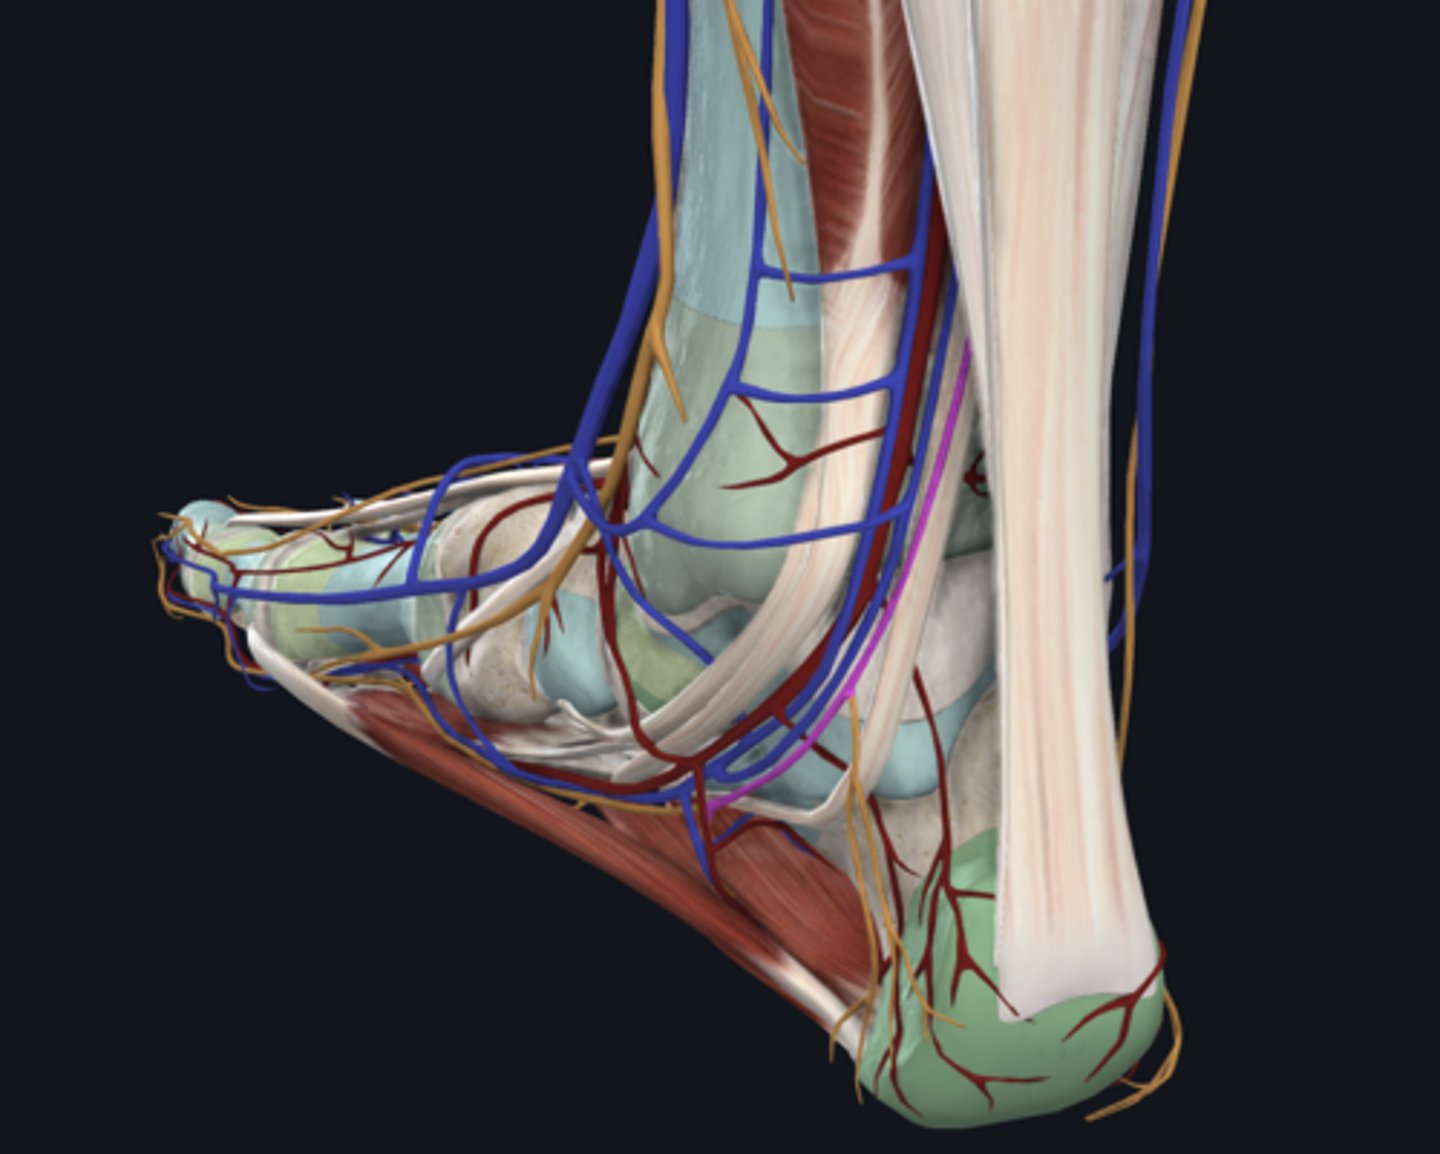

Flexor digitorum longus

tendon in tarsal tunnel

Flexor hallucis longus

tendon in tarsal tunnel

Tibialis posterior

tendon in tarsal tunnel

Tibial nerve (in tarsal tunnel)

nerve

Posterior tibial artery (in tarsal tunnel)

artery

Posterior tibial vein (in tarsal tunnel)

vein